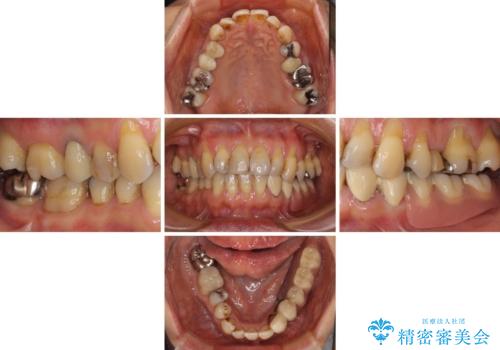

入れ歯の支台となっていたコーヌスのゴールドも除去し、インプラント部と合わせてオールセラミッククラウンにて補綴治療を行うこととしました。

インプラント埋入後、必要以上に傷口に歯ブラシを当てすぎてしまったことで歯肉の炎症が続き、それに伴いインプラント周辺の骨が若干吸収してしまいました。それでも術後の経過は良好で、違和感や不具合なく使用できています。